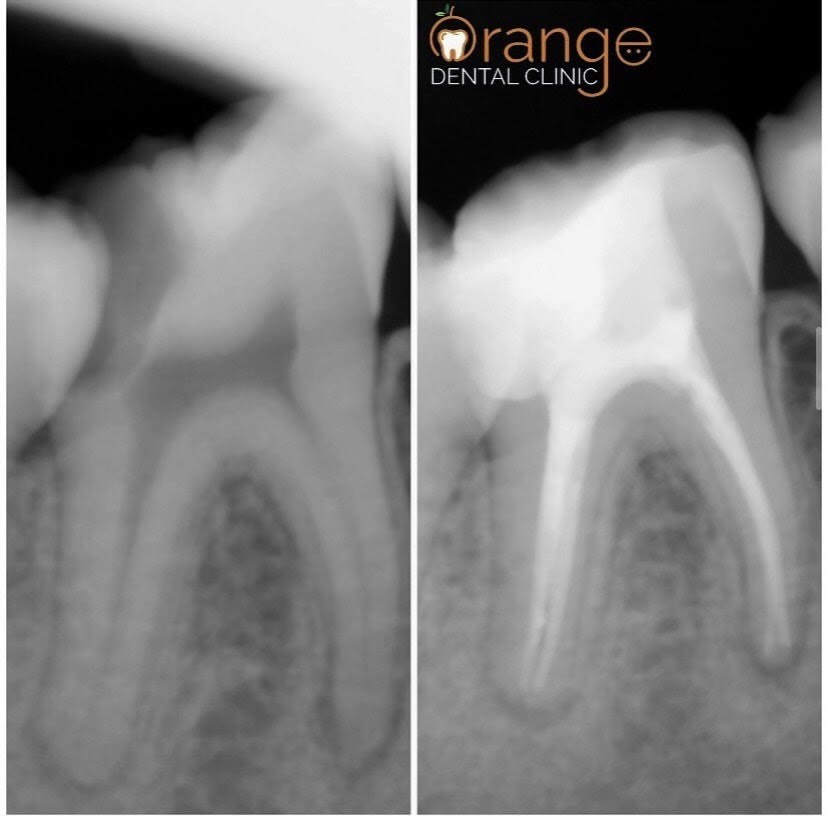

RADIOGRAPHIC CASE PRESENTATION

Root Canal Treatment Treatment